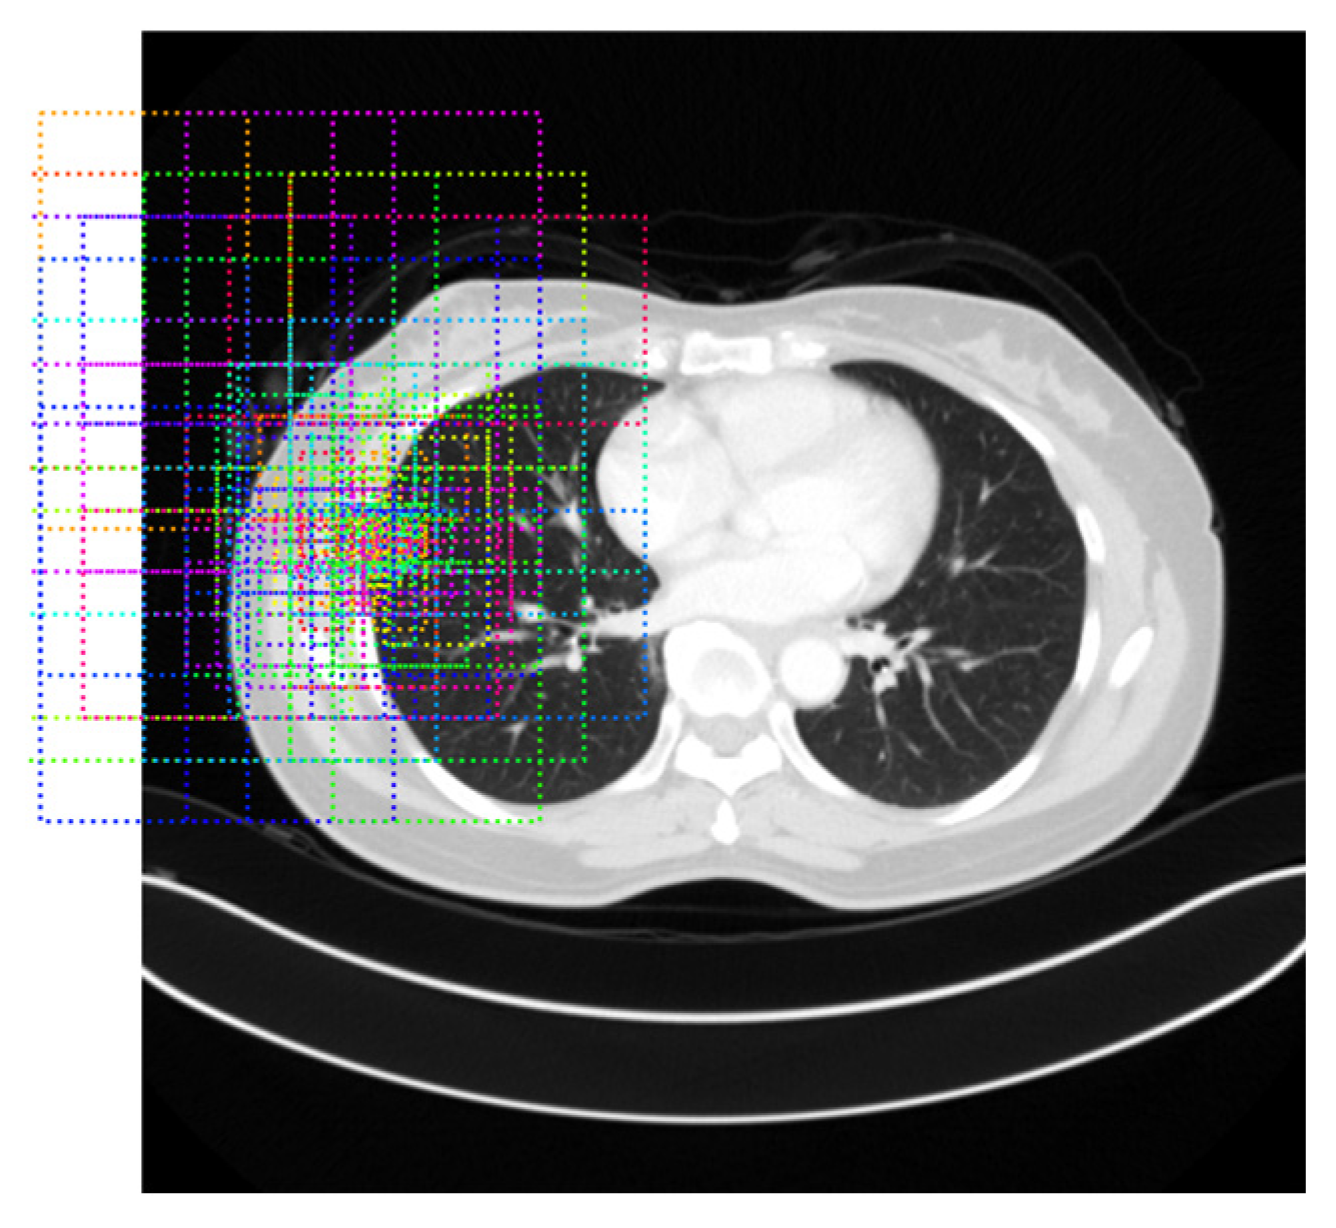

Thresholding-Based Morphology for Semi-Automated Segmentation

3.2.4. Illustrative Examples of Segmentation Results